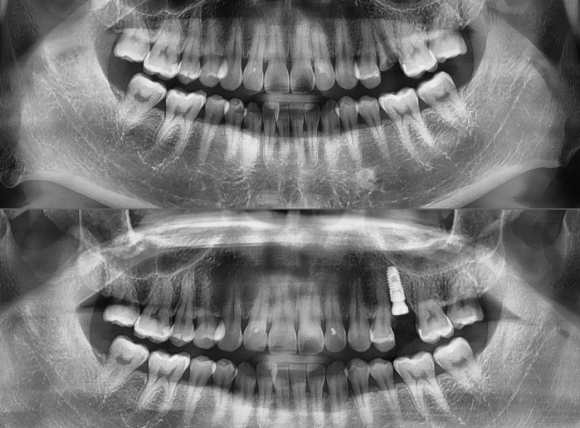

해당 임플란트를 진행한 치아는 치아가 뿌리까지 심하게 파절되어 어떠한 방식으로도 살릴 수 없는 치아이기 때문에 발치 후 임플란트 당일 식립을 진행하였습니다. 치아 발치 시 주변 뼈가 다치지 않도록 조심스럽게 발치 후, 충분한 양과 깨끗한 뼈가 존재하고 있기 때문에 당일에 임플란트를 식립할 수 있었습니다....

해당 임플란트를 진행한 치아는 치아가 뿌리까지 심하게 파절되어

어떠한 방식으로도 살릴 수 없는 치아이기 때문에

발치 후 임플란트 당일 식립을 진행하였습니다.

치아 발치 시 주변 뼈가 다치지 않도록 조심스럽게 발치 후,

충분한 양과 깨끗한 뼈가 존재하고 있기 때문에

당일에 임플란트를 식립할 수 있었습니다.

식립한 임플란트 뿌리와 뼈가 잘 결합할 수 있도록

3~4개월의 충분한 시간을 기다린 후

머리를 올려서 기능을 할 수 있도록 만들 예정입니다.